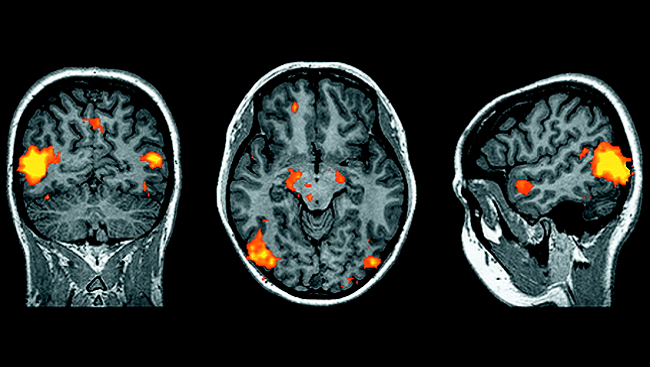

The big breakthrough in narcolepsy research came in 1998 when two teams of scientists working in separate laboratories discovered a previously unknown protein in a few cells of the hypothalamus, a brain region that controls many metabolic functions, including body temperature, hunger, thirst — and sleep. This protein, orexin (also called hypocretin), promotes arousal and wakefulness and inhibits REM sleep, the intervals during sleep when dreams occur and when muscles become inactive.